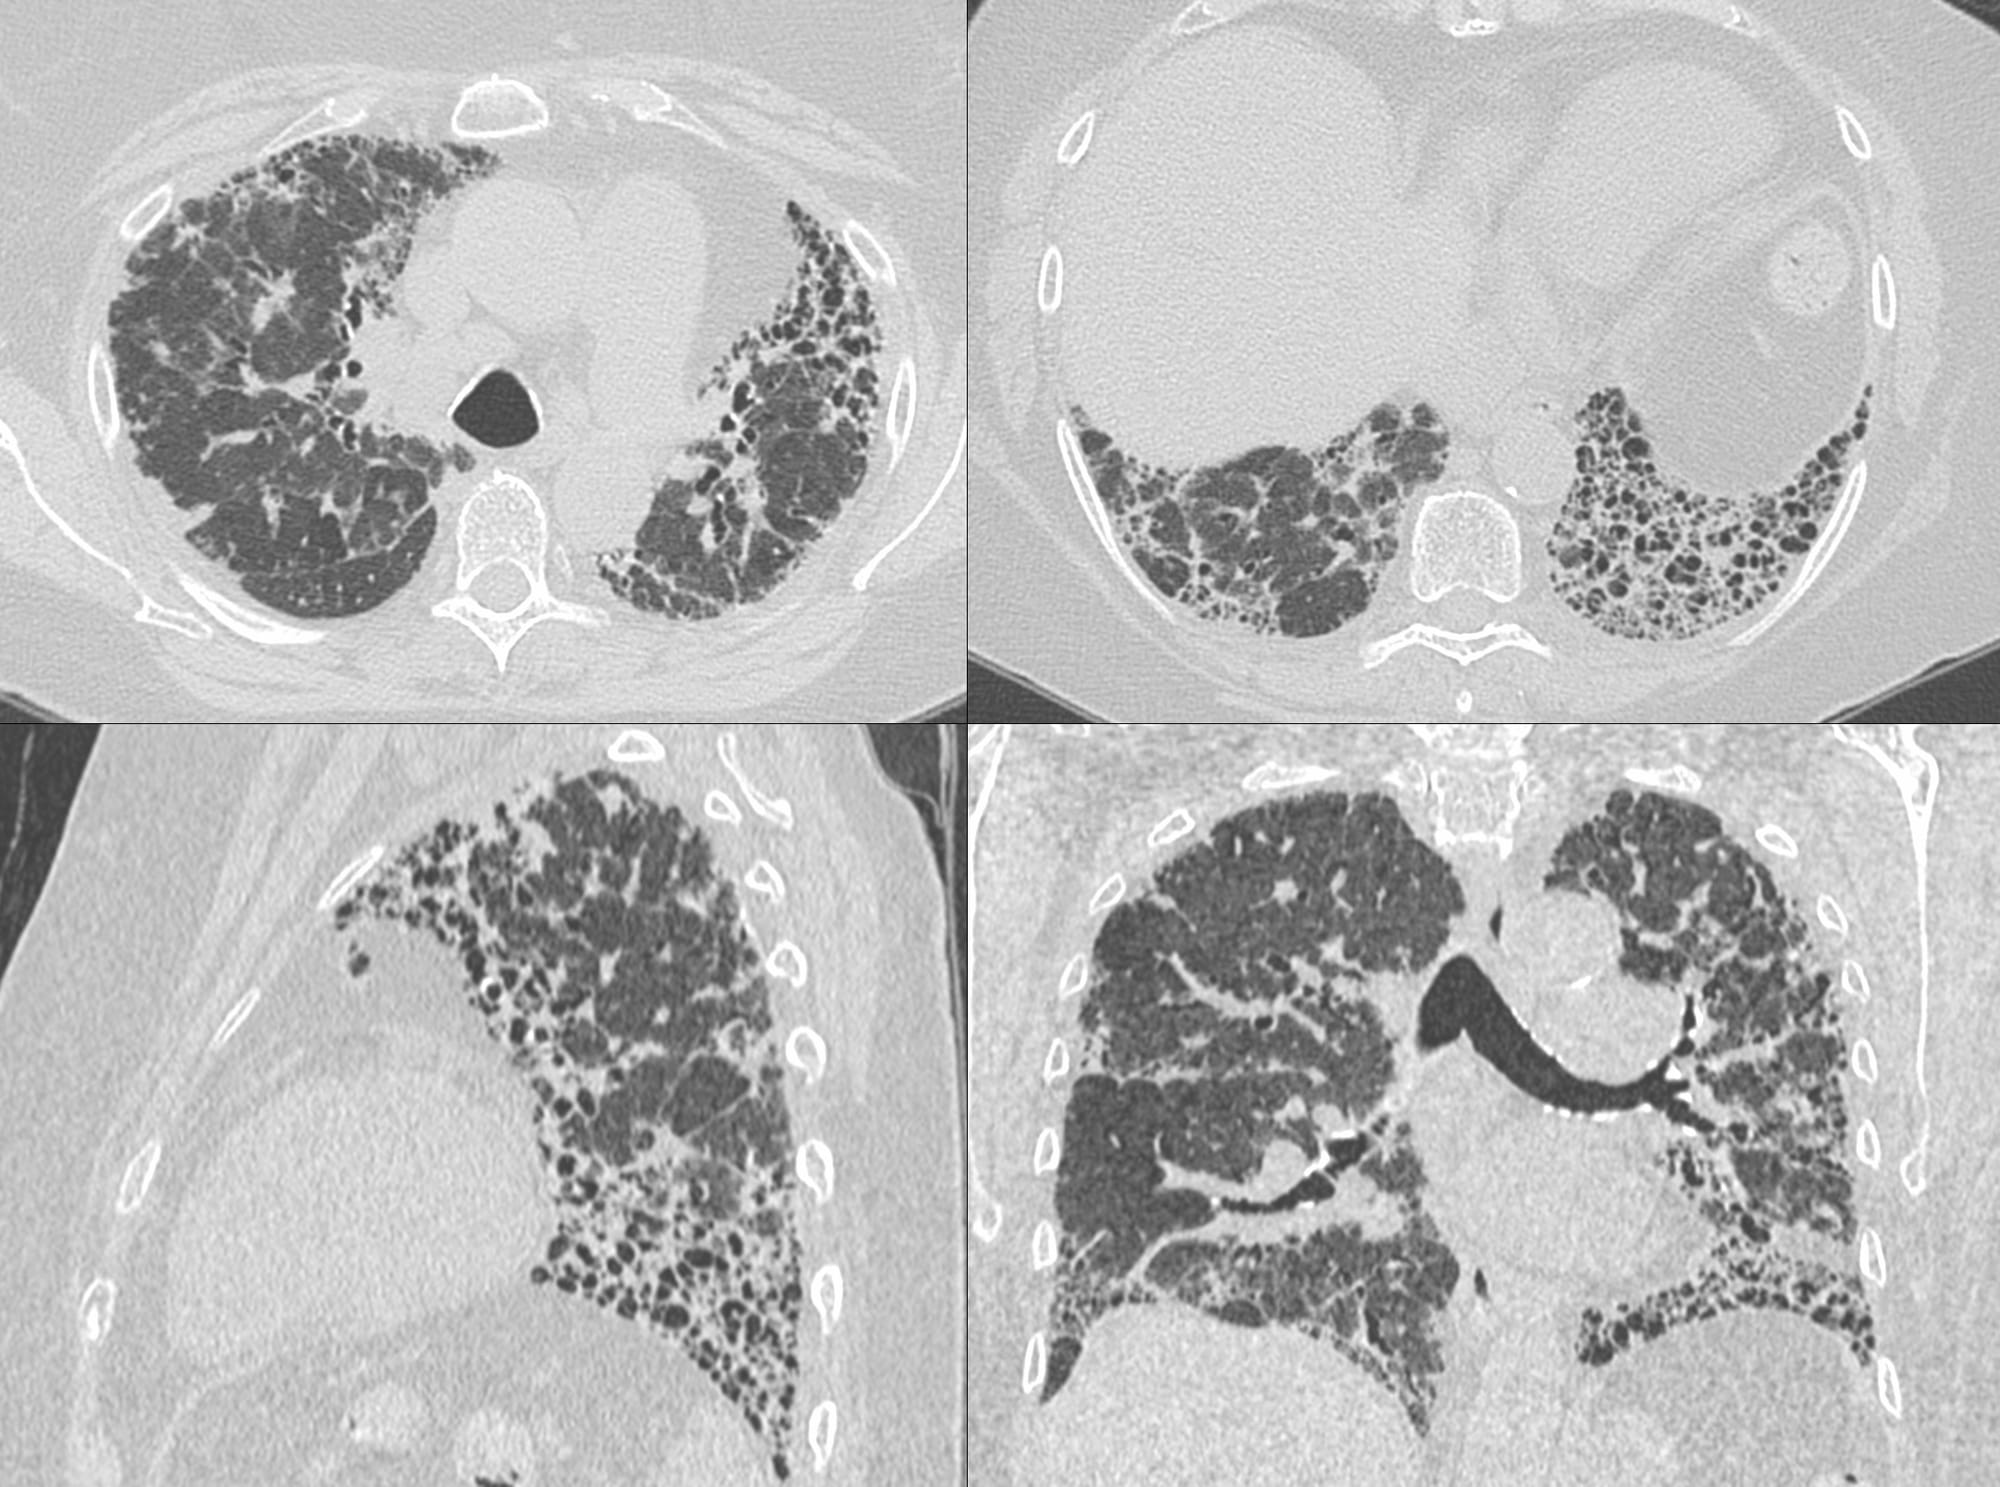

70-years old with a fibrosing ILD that shows a usual interstitial pneumonia (UIP) - like pattern on the left, but a three-density sign on the right suggesting this could be a bronchiolocentric interstitial pneumonia (BIP) pattern, suggestive of fibrotic hypersensitivity pneumonitis, if there is no underlying etiology (Fig. 1).